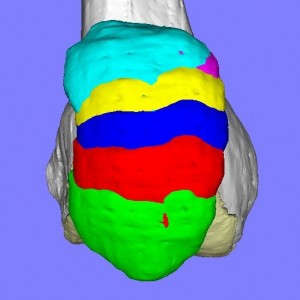

膝蓋骨脱臼には様々なパターンがあり、患者それぞれの膝蓋骨の動きのパターンを評価して適切な手術方法を検討します。

膝蓋骨の動きには上図のように様々なパターンが存在します。(我々の研究結果から)